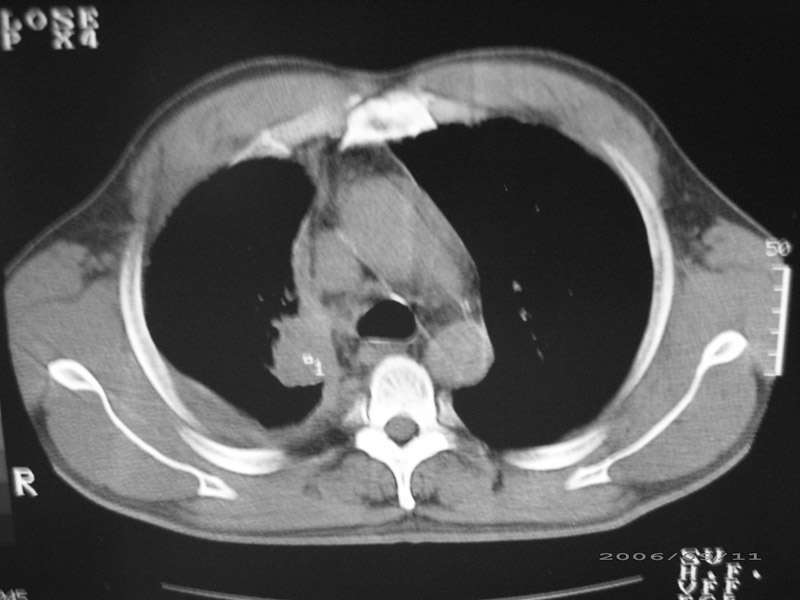

以下是引用守望可可西里在2006-9-11 15:29:00的发言:[br][br] ct平扫表现:右侧胸膜腔缩小,积液,胸膜增厚且不均匀、不规则,以纵隔胸膜增厚为主,边缘呈锯齿状,并见附壁内突之结节状肿块影。右肺含气量减少,纹理聚集,右肺门中下部见数个肿大的淋巴结。纵隔无移位,内未见明显肿大淋巴结,双侧主支气管以及各叶、段支气管比较通畅。。[br] 考虑:右侧胸膜恶性间皮瘤,伴肺门淋巴结转移。